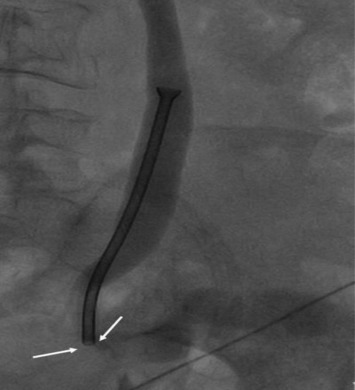

Subsequently, a decision was made by the urology team to replace the double J stent with a Memokath 051 stent (PNN A/S, Hornbaek, Denmark) endoscopically, via fluoroscopic guidance. The Memokath stent used was 10 cm in length with a 10.5 F inner lumen size and 20 F expanded lumen size at the funnel. The procedure was performed under general anesthesia, with the patient placed in a supine position, and with preoperative antibiotics coverage. A conduitoscopy was performed using a cystoscope, and it showed a tumor at the anastomotic site with the tip of the double J stent in situ. Biopsies of the tumor were performed, and the double J stent was partially pulled out. Subsequently, a guidewire was threaded up into the right pelvicalyceal system via the indwelling double J stent. After the removal of the double J stent and prior to the Memokath stent insertion, over the guidewire, the malignant stricture was dilated with serial ureteric dilators and Memokath sheath. However, because of the unfavorable angulation of the ureteroileal junction and inaccurate assessment of stricture length, the stent was suboptimally positioned. Following warm saline deployment, the distal end of the stent was noted to be lying above the stricture ( Fig. 1). Attempts to retrieve the stent failed, as the endoscope could not be passed across the malignant stricture.

Right nephrostogram showing a Memokath 051 stent in a dilated ureter. The distal ...

Right nephrostogram showing a Memokath 051 stent in a dilated ureter. The distal tip of the stent is located just above the stricture (arrows).